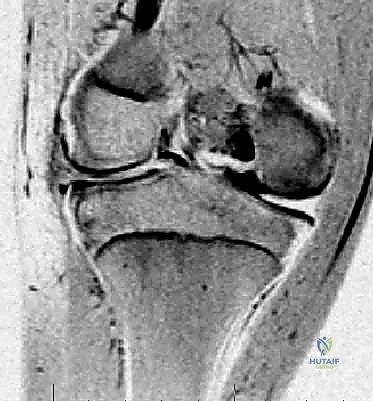

- التصوير بالرنين المغناطيسي (MRI): هو المعيار الذهبي لتشخيص الغضروف الهلالي القرصي. يتيح الرنين المغناطيسي رؤية تفصيلية للأنسجة الرخوة. يبحث الدكتور هطيف عن علامات محددة في الرنين، مثل "علامة ربطة العنق" (Bow-tie sign) التي تظهر في أكثر من 3 مقاطع متتالية، مما يؤكد زيادة عرض الغضروف. كما يوضح الرنين بدقة وجود أي تمزقات مصاحبة أو غياب الأربطة المثبتة (نوع وريسبيرغ).